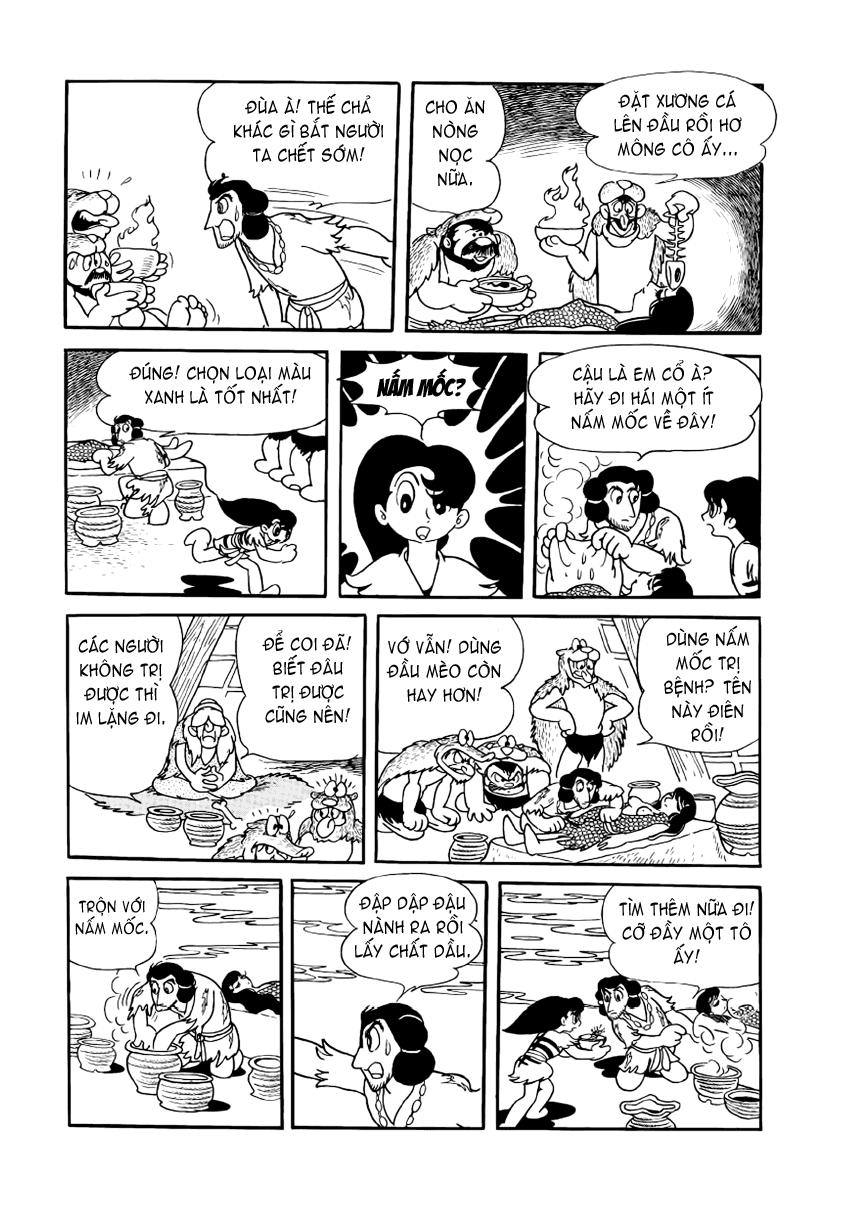

23-02-2017 17:05:45 GMT+7 20-12-2023 04:08:25 GMT+7Có một truyền thuyết cổ xưa về Hi no tori (Chim lửa), rằng bất kì ai uống máu loài chim này sẽ trở nên bất tử, đây là loài chim của thần thá Vì thế, những người vọng tưởng sự trường sinh bất lão luôn tìm kiếm và săn bắt loài chim ấy. Con chim lửa ấy bay mãi, nối liền từ quá khứ tới tương lai, nối liền những câu chuyện về ái hận sân si của những con người tưởng chừng như chẳng liên quan tới nhau, nhưng thật ra bản thể chỉ lại là một. Chim lửa , nó chết đi, rồi lại tái sinh trong tro tàn, sự tồn tại của nó là một vòng luân hồi bất tận. Sự tồn tại của con người và thế giới này cũng vậy, con người sinh ra, chết đi, và lại sinh ra ở một kiếp khác; thế giới diệt vong, rồi lại tái sinh; nghiệt này gieo xuống, nhân kia trả lại; và 12 câu chuyện trong Hi no tori cũng thế, tưởng như rời rạc nhưng thực ra lại kết lại thành một vòng tròn luân hồi… Và bắt đầu cho vòng tròn ấy là Bình minh, câu chuyện về tham vọng trường sinh bất tử của nữ vương Himiko.